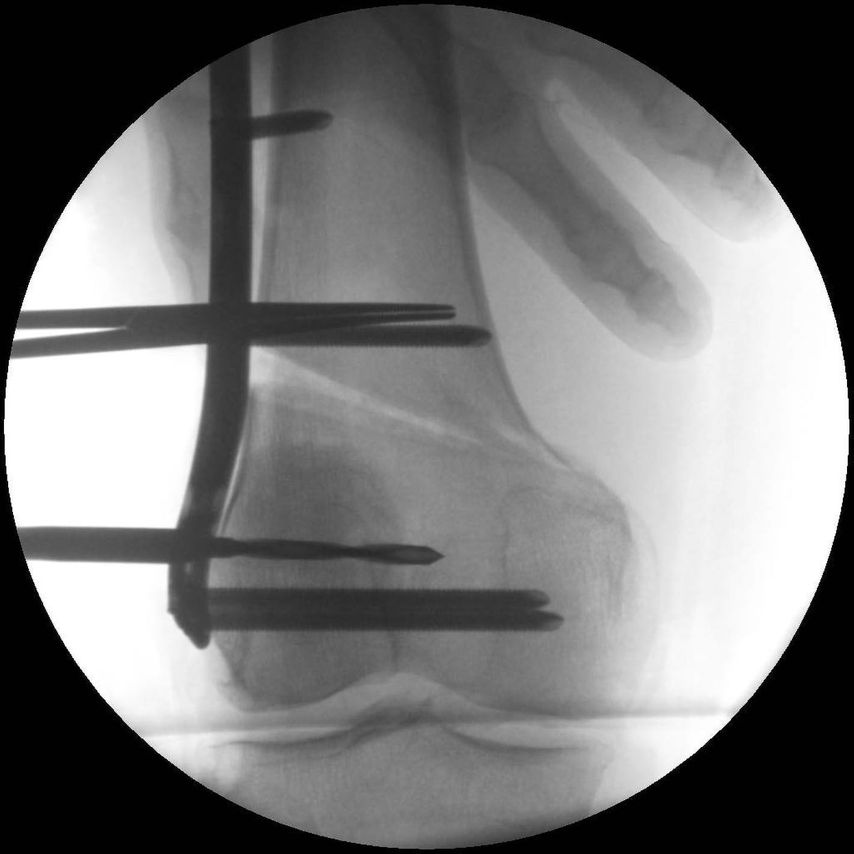

17-jähriger Patient mit wiederkehrenden Patellaluxationen

Aufgrund eines erhöhten Caton-Deschamps-Index von >1,2 erfolgten die Tuberositasdistalisierung und die MPFL-Plastik mit der Gracillissehne (Abb. 2 und 3). Ca. 4 Wochen nach dem operativen Eingriff stürzte der Patient auf das rechte Kniegelenk mit Mehrfragmentbruch des Tuberositasfragments (Abb. 4). Die neuerliche Fixierung erfolgte mittels 3,5mm-Drittelrohrverplattung sowie, wegen des Mehrfragmentbruches im proximalen Bereich, mittels Durchflechtungsnaht und Knochenankern (Abb. 5).